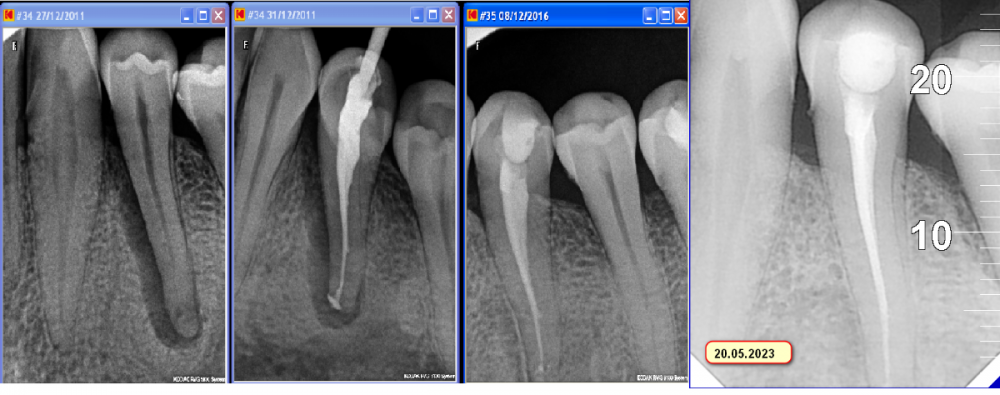

Большой Зеленый Опубликовано 25 мая, 2023 Автор Поделиться Опубликовано 25 мая, 2023 Праздник тот же день второй.... всмысле 12 лет полет нормальный )) 3 Ссылка на комментарий

Большой Зеленый Опубликовано 25 мая, 2023 Автор Поделиться Опубликовано 25 мая, 2023 Случайно попал на осмотр пациент .Уговорил его сделать контрольный снимок. Говорю нехорошо делать такое эндо. Денег больше не принесет))) Поржали конечно. Приятно видеть .Даже пломба та же. 1 Ссылка на комментарий